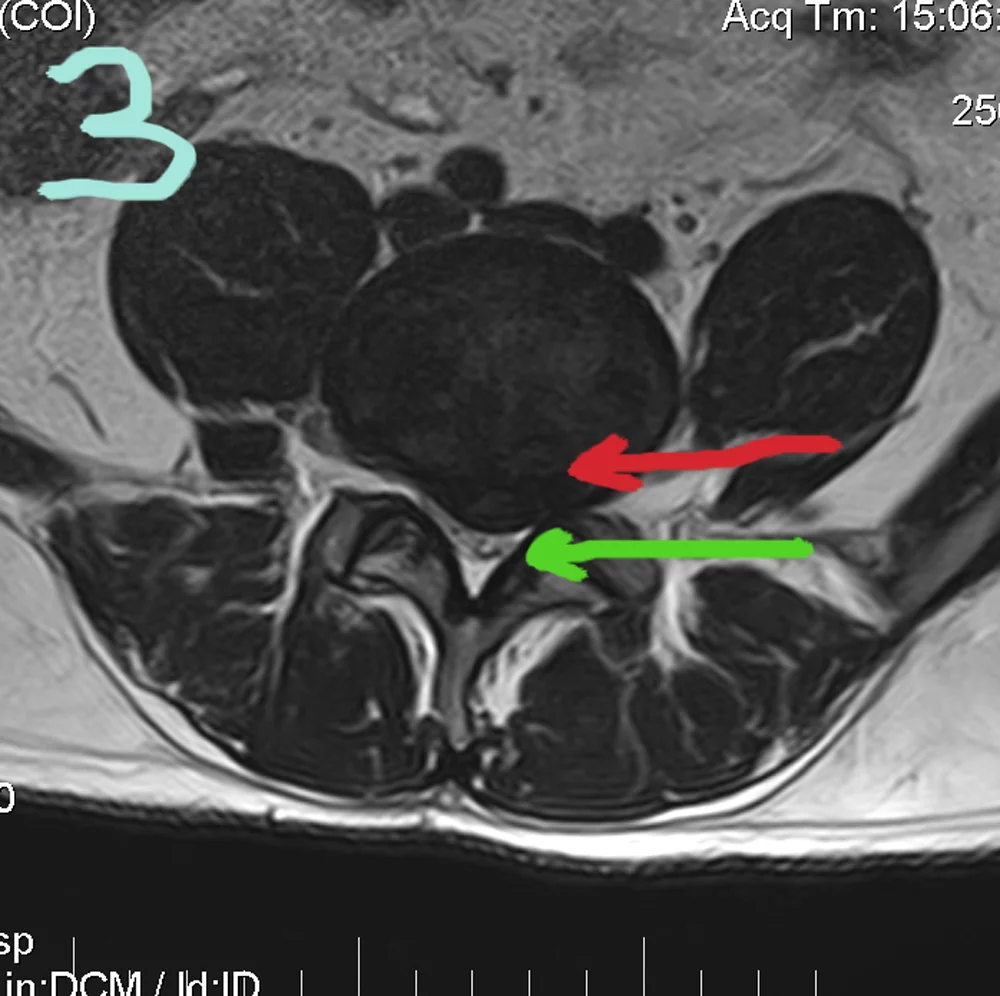

Картинки про то, как грыжа может сдавить нерв.

Вкладення

• 2.webp

2.webp

57.7 КБ · Перегляди: 147

• 3.webp

3.webp

58 КБ · Перегляди: 129